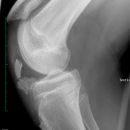

Tibiakopffraktur (nicht disloziert)